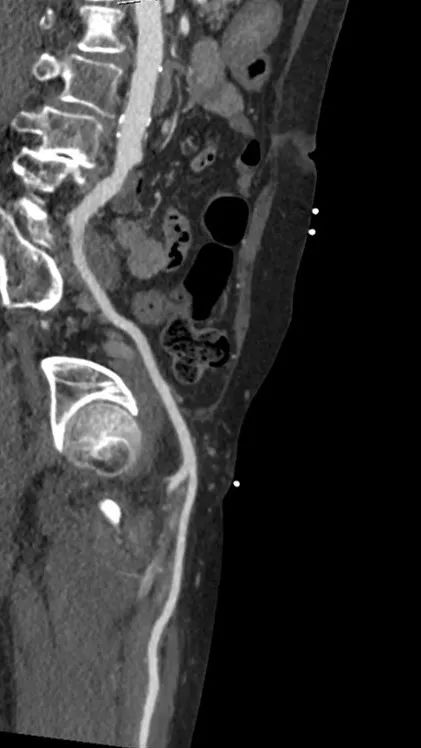

术后1w——冠脉CTA